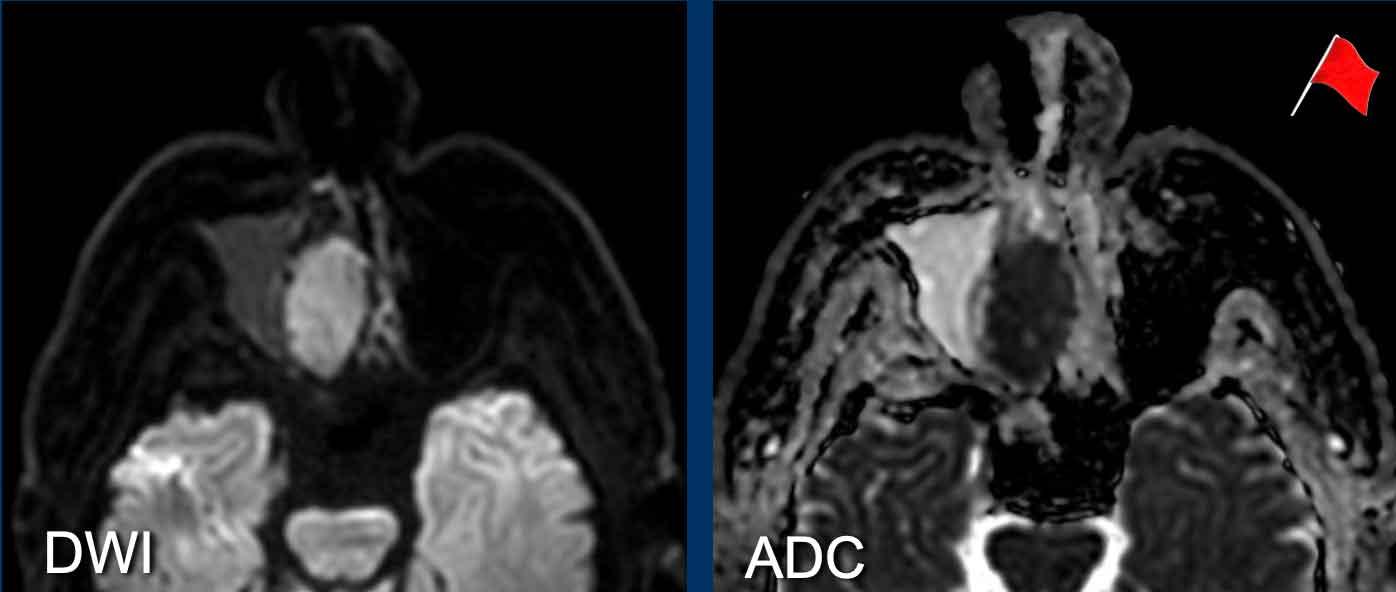

Trên hình ảnh khuếch tán, tổn thương có tín hiệu cao trên b1000.

Trên bản đồ ADC, tổn thương có tín hiệu rất thấp, thậm chí thấp hơn cả mô não, gợi ý tình trạng hạn chế khuếch tán rõ rệt.

Điều này có nghĩa là chúng ta đang đối mặt với một khối u tăng mật độ tế bào.

Đây là dấu hiệu cảnh báo thứ ba.

Tiếp tục xem hình ảnh MRI…

Hình ảnh MRI cho thấy một khối u một bên trong hốc mũi phải gây tắc nghẽn xoang trán và ở mức độ thấp hơn là xoang hàm.

Có hiện tượng hạn chế khuếch tán (tăng tín hiệu trên DWI và giảm tín hiệu trên ADC) — đây là dấu hiệu cảnh báo thứ ba.

Sinh thiết xác nhận ung thư biểu mô tuyến.

Bệnh nhân được điều trị bằng phẫu thuật cắt bỏ kết hợp xạ trị proton và hiện không còn bằng chứng bệnh trong 14 tháng.

MRI cho thấy một khối u phá hủy một bên với hạn chế khuếch tán rõ rệt (giảm tín hiệu trên bản đồ ADC).

Như vậy, chúng ta có ba dấu hiệu cảnh báo.

Hạn chế khuếch tán là một lập luận khác chống lại chẩn đoán u xơ mạch máu vị thành niên, vì một tổn thương mạch máu sẽ không gây ra hạn chế khuếch tán.

Có xâm lấn vào hốc mắt và cả vào phần mềm phía trước của má (mũi tên).

Sinh thiết được thực hiện và cho kết quả là u cơ vân (rhabdomyosarcoma), được điều trị bằng hóa trị liệu.